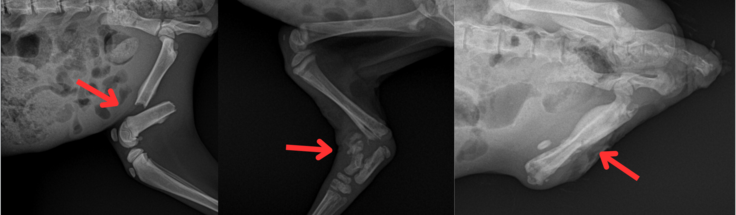

診察の結果、3頭のうち:

はやては骨折状態でしたが、感染はなく整復・固定による治療が可能と判断され、協力動物病院にて治療を実施。

一方、はやぶさとのぞみは、骨折部に感染が強く起きており、後ろ足の断脚手術が必要となりました。

【レントゲン写真 左:はやて 中央:はやぶさ 右:のぞみ】